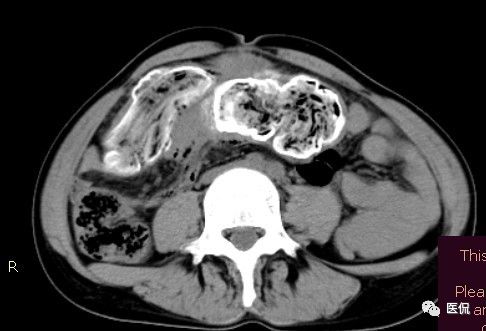

腹腔内残留的纱布在人体内引起渗出或液化坏死并纤维包裹形成异物性脓肿(纱布瘤)。纱布瘤的影像特点:圆形或卵圆形肿块,较大,有完整包膜,薄壁,较少的情况下为厚壁,边界较完整,增强后薄膜可以持续强化。不同时期的纱布瘤可以有不同表现:早期(10个月或半年内)多表现为蜂窝状;2~5年内一般表现为囊性飘带状;10~20年之后则为实性软组织密度,包膜钙化呈钙化网状结构。手术过程中残留在人体内的医用纱布所形成的肿瘤样病变。

腹腔内遗留纱布团的影像学表现,以B超较具特征性,其主要表现为:腹腔或盆腔内特殊率减的黑色包块,后方伴有扇形衰减的声影,上窄下宽,好似一“黑色大布”,早期包块内含有不规则光团或光点,随时间延长有缩小或消失,为纱布团内气体。CT的优势在于早期常表现为软组织密度的肿块,其内可见多少不等的气泡,随时间的延长气泡逐渐被吸收减少至消失,增强扫描可见包膜不同程度强化而内容物无强化。熟悉其影像学表现,可在术前作出明确诊断。